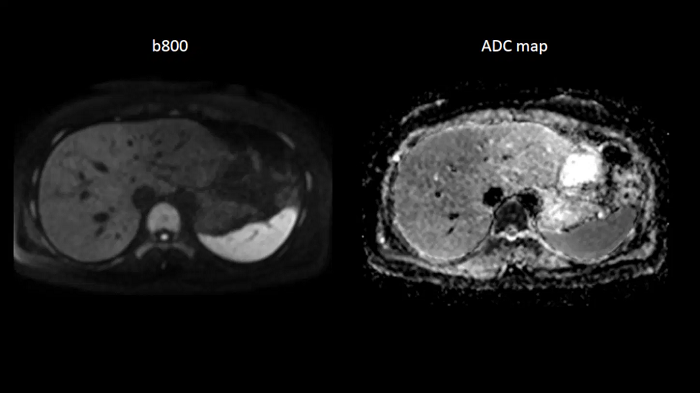

Body diffusion imaging

For all-inclusive abdominal MR capabilities, outstanding quality diffusion imaging.

MAC-ID: 7aaaa0165. Image Credit: Siemens Healthineers